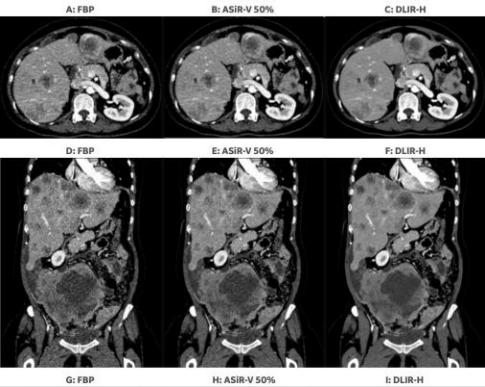

图为腹部及盆腔多发转移性肿瘤患者用CT进行检查,分别采用传统FBP,ASiR-V和GE独有DLIR重建层厚0.625mm的图像。无论是轴位,冠状位或是矢状位,DLIR在降噪,保留噪声纹理及更好的显示肿瘤病变的边界及内部结构方面均有优越的表现。